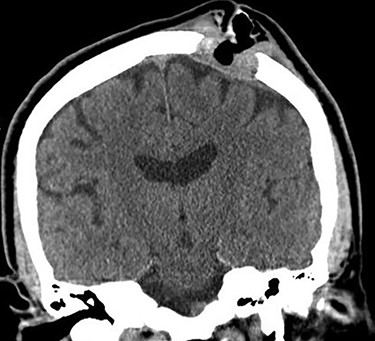

Noncontrast head computed tomography (CT) confirmed a left parietal bone lytic lesion (Fig. 1). Brain magnetic resonance imaging (MRI) confirmed an enhancing mass involving the left lateral scalp and parietal bone extending down to the dura (Fig. 2). T1-weighted image noted additional small enhancing lesions of the frontal calvarium. Initial laboratory studies noted hypercalcemia (serum calcium 10.6 mg/dl) and anemia (hemoglobin 11.5 g/dl).

Head CT without contrast (coronal plane) showing a 3.3-cm lytic lesion of the left parietal calvarium with extension of soft tissue hyperdensity to the dural surface.